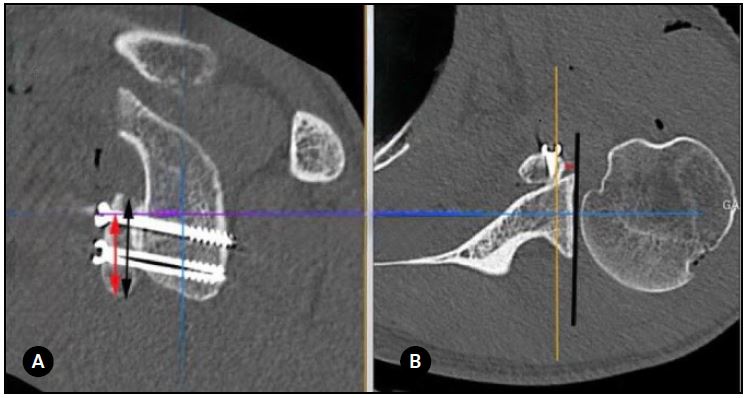

Se mostraron simultáneamente en la misma pantalla las imágenes en 2 planos (sagital y axial). Luego se realizaron las siguientes 4 medidas para cada paciente: (A) la posición del injerto coracoideo en el plano sagital, (B) la posición del injerto en el plano axial, (C) la dirección de los tornillos (ángulo), y (D) el ángulo de contacto (Figs. 1 y 2).

La posición del injerto coracoideo en el plano sagital se definió como el porcentaje del injerto ubicado debajo del ecuador de la cavidad glenoidea. Dividimos los resultados en 4 grupos: A (80-100 % por debajo del ecuador), B (60-79 %), C (40-59 %) y D (<40 %).

En el plano axial, el injerto coracoideo se consideró “al ras” cuando el borde lateral del injerto estaba entre 1 mm lateral y 4 mm medial a la línea articular; “medial” cuando estaba >4 mm medial a la línea articular; y “prominente” cuando era >1 mm lateral a la línea articular. El ángulo α se definió como el ángulo entre el eje del tornillo y el hueso subcondral glenoideo. Finalmente, el ángulo de contacto fue el ángulo formado entre la superficie posterior del injerto coracoideo (medido entre los 2 tornillos) y el cuello anterior de la glena. Se consideró contacto completo si el ángulo era ≤4 e incompleto cuando era >4. Si el espacio entre el injerto y la glenoides era >1 mm, asumimos que no existía contacto.16

Figura 1. Evaluación del injerto coracoideo. A) Plano sagital en relación con el ecuador de la glena. La flecha negra indica la longitud total del injerto coracoideo, mientras que la flecha roja muestra la parte del injerto que se encuentra debajo del ecuador glenoideo. B) Plano axial (posición mediolateral). La línea negra es tangente al hueso subcondral de la glenoides mientras que la línea roja indica la distancia entre la línea negra y la cara más lateral del injerto coracoideo.